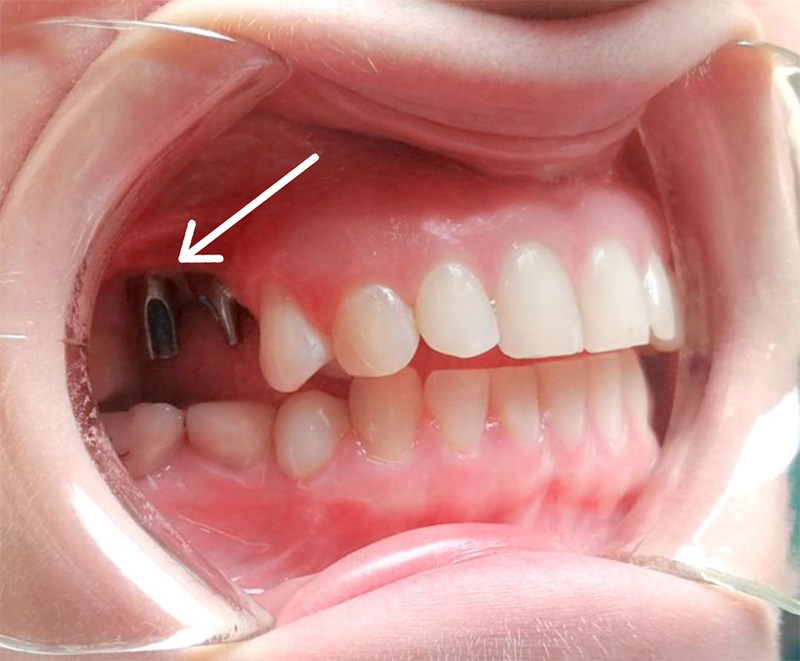

Июль. Протезирование

Выполненные манипуляции:

- R-контроль приживления имплантов - 700 ₽

- Снятие формирователя десны - бесплатно

- Установка в имплант абатмента - 3 × 9 500 ₽. На фото видны абатменты (похожи на обточенный зуб)

- Снятие слепков с 2 челюстей - 2 × 7 500 ₽

- Изготовление металлокерамических коронок 3 × 22 000 ₽

- Фиксация готовых коронок на абатмент 3 × 1 500 ₽

Итого: 113 700 ₽